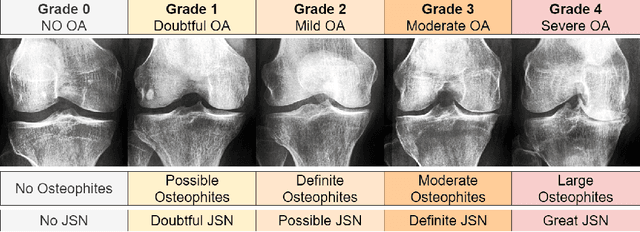

Abstract:Knee-Joint Osteoarthritis (KOA) is a prevalent cause of global disability and is inherently complex to diagnose due to its subtle radiographic markers and individualized progression. One promising classification avenue involves applying deep learning methods; however, these techniques demand extensive, diversified datasets, which pose substantial challenges due to medical data collection restrictions. Existing practices typically resort to smaller datasets and transfer learning. However, this approach often inherits unnecessary pre-learned features that can clutter the classifier's vector space, potentially hampering performance. This study proposes a novel paradigm for improving post-training specialized classifiers by introducing adaptive variance thresholding (AVT) followed by Neural Architecture Search (NAS). This approach led to two key outcomes: an increase in the initial accuracy of the pre-trained KOA models and a 60-fold reduction in the NAS input vector space, thus facilitating faster inference speed and a more efficient hyperparameter search. We also applied this approach to an external model trained for KOA classification. Despite its initial performance, the application of our methodology improved its average accuracy, making it one of the top three KOA classification models.

Abstract:Knee Osteoarthritis (KOA), a leading cause of disability worldwide, is challenging to detect early due to subtle radiographic indicators. Diverse, extensive datasets are needed but are challenging to compile because of privacy, data collection limitations, and the progressive nature of KOA. However, a model capable of projecting genuine radiographs into different OA stages could augment data pools, enhance algorithm training, and offer pre-emptive prognostic insights. In this study, we trained a CycleGAN model to synthesize past and future stages of KOA on any genuine radiograph. The model was validated using a Convolutional Neural Network that was deceived into misclassifying disease stages in transformed images, demonstrating the CycleGAN's ability to effectively transform disease characteristics forward or backward in time. The model was particularly effective in synthesizing future disease states and showed an exceptional ability to retroactively transition late-stage radiographs to earlier stages by eliminating osteophytes and expanding knee joint space, signature characteristics of None or Doubtful KOA. The model's results signify a promising potential for enhancing diagnostic models, data augmentation, and educational and prognostic usage in healthcare. Nevertheless, further refinement, validation, and a broader evaluation process encompassing both CNN-based assessments and expert medical feedback are emphasized for future research and development.

Abstract:Diagnosing knee joint osteoarthritis (KOA), a major cause of disability worldwide, is challenging due to subtle radiographic indicators and the varied progression of the disease. Using deep learning for KOA diagnosis requires broad, comprehensive datasets. However, obtaining these datasets poses significant challenges due to patient privacy concerns and data collection restrictions. Additive data augmentation, which enhances data variability, emerges as a promising solution. Yet, it's unclear which augmentation techniques are most effective for KOA. This study explored various data augmentation methods, including adversarial augmentations, and their impact on KOA classification model performance. While some techniques improved performance, others commonly used underperformed. We identified potential confounding regions within the images using adversarial augmentation. This was evidenced by our models' ability to classify KL0 and KL4 grades accurately, with the knee joint omitted. This observation suggested a model bias, which might leverage unrelated features for classification currently present in radiographs. Interestingly, removing the knee joint also led to an unexpected improvement in KL1 classification accuracy. To better visualize these paradoxical effects, we employed Grad-CAM, highlighting the associated regions. Our study underscores the need for careful technique selection for improved model performance and identifying and managing potential confounding regions in radiographic KOA deep learning.